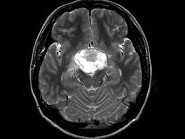

- 单项选择题男,27岁, 头痛、双眼视力下降、多饮、多尿4个月,根据所提供图像, 最可能的诊断是 ( )

A、颅咽管瘤

B、垂体瘤

C、生殖细胞瘤

D、胶质瘤

E、神经鞘瘤